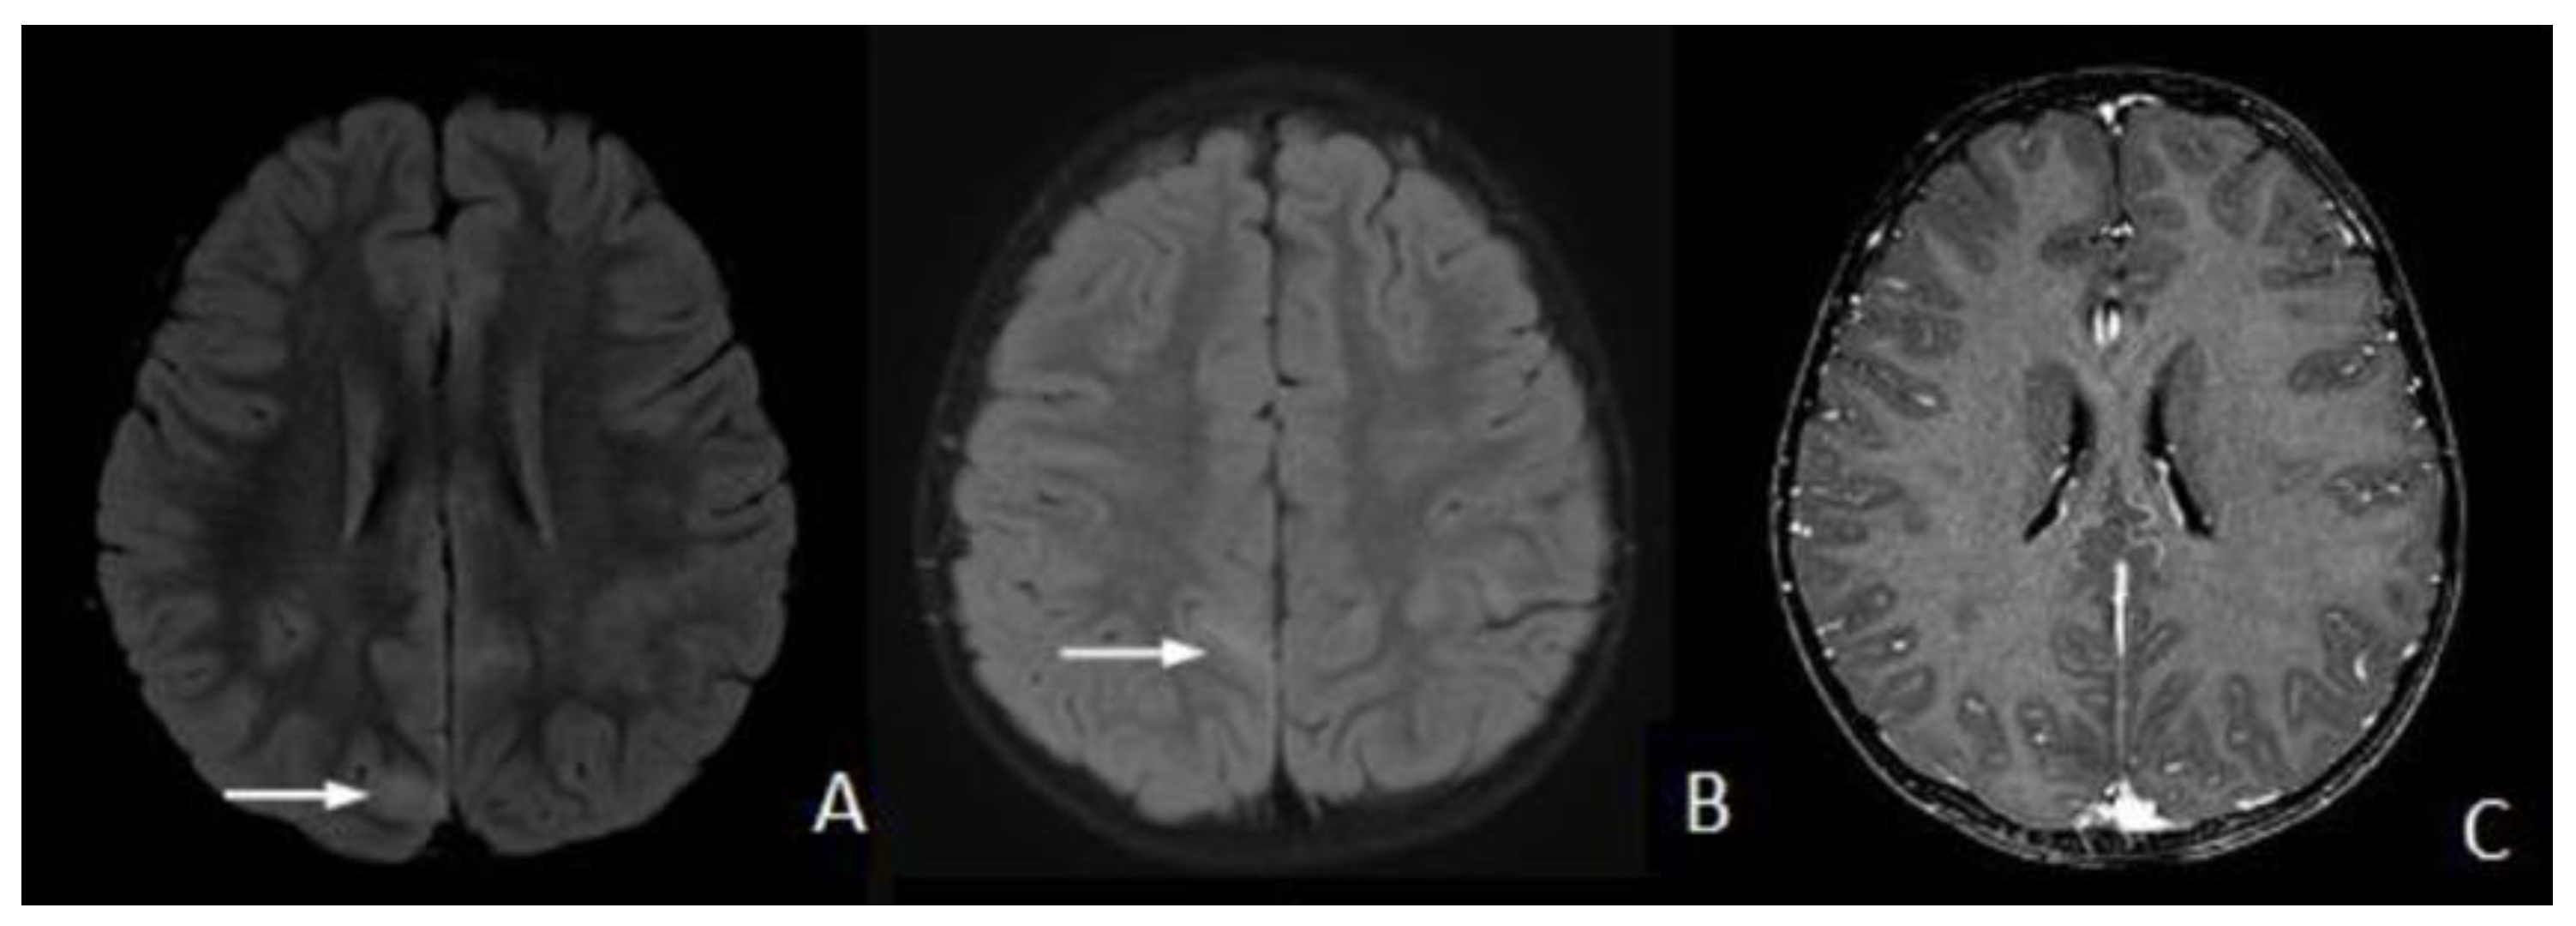

2. Case Presentation